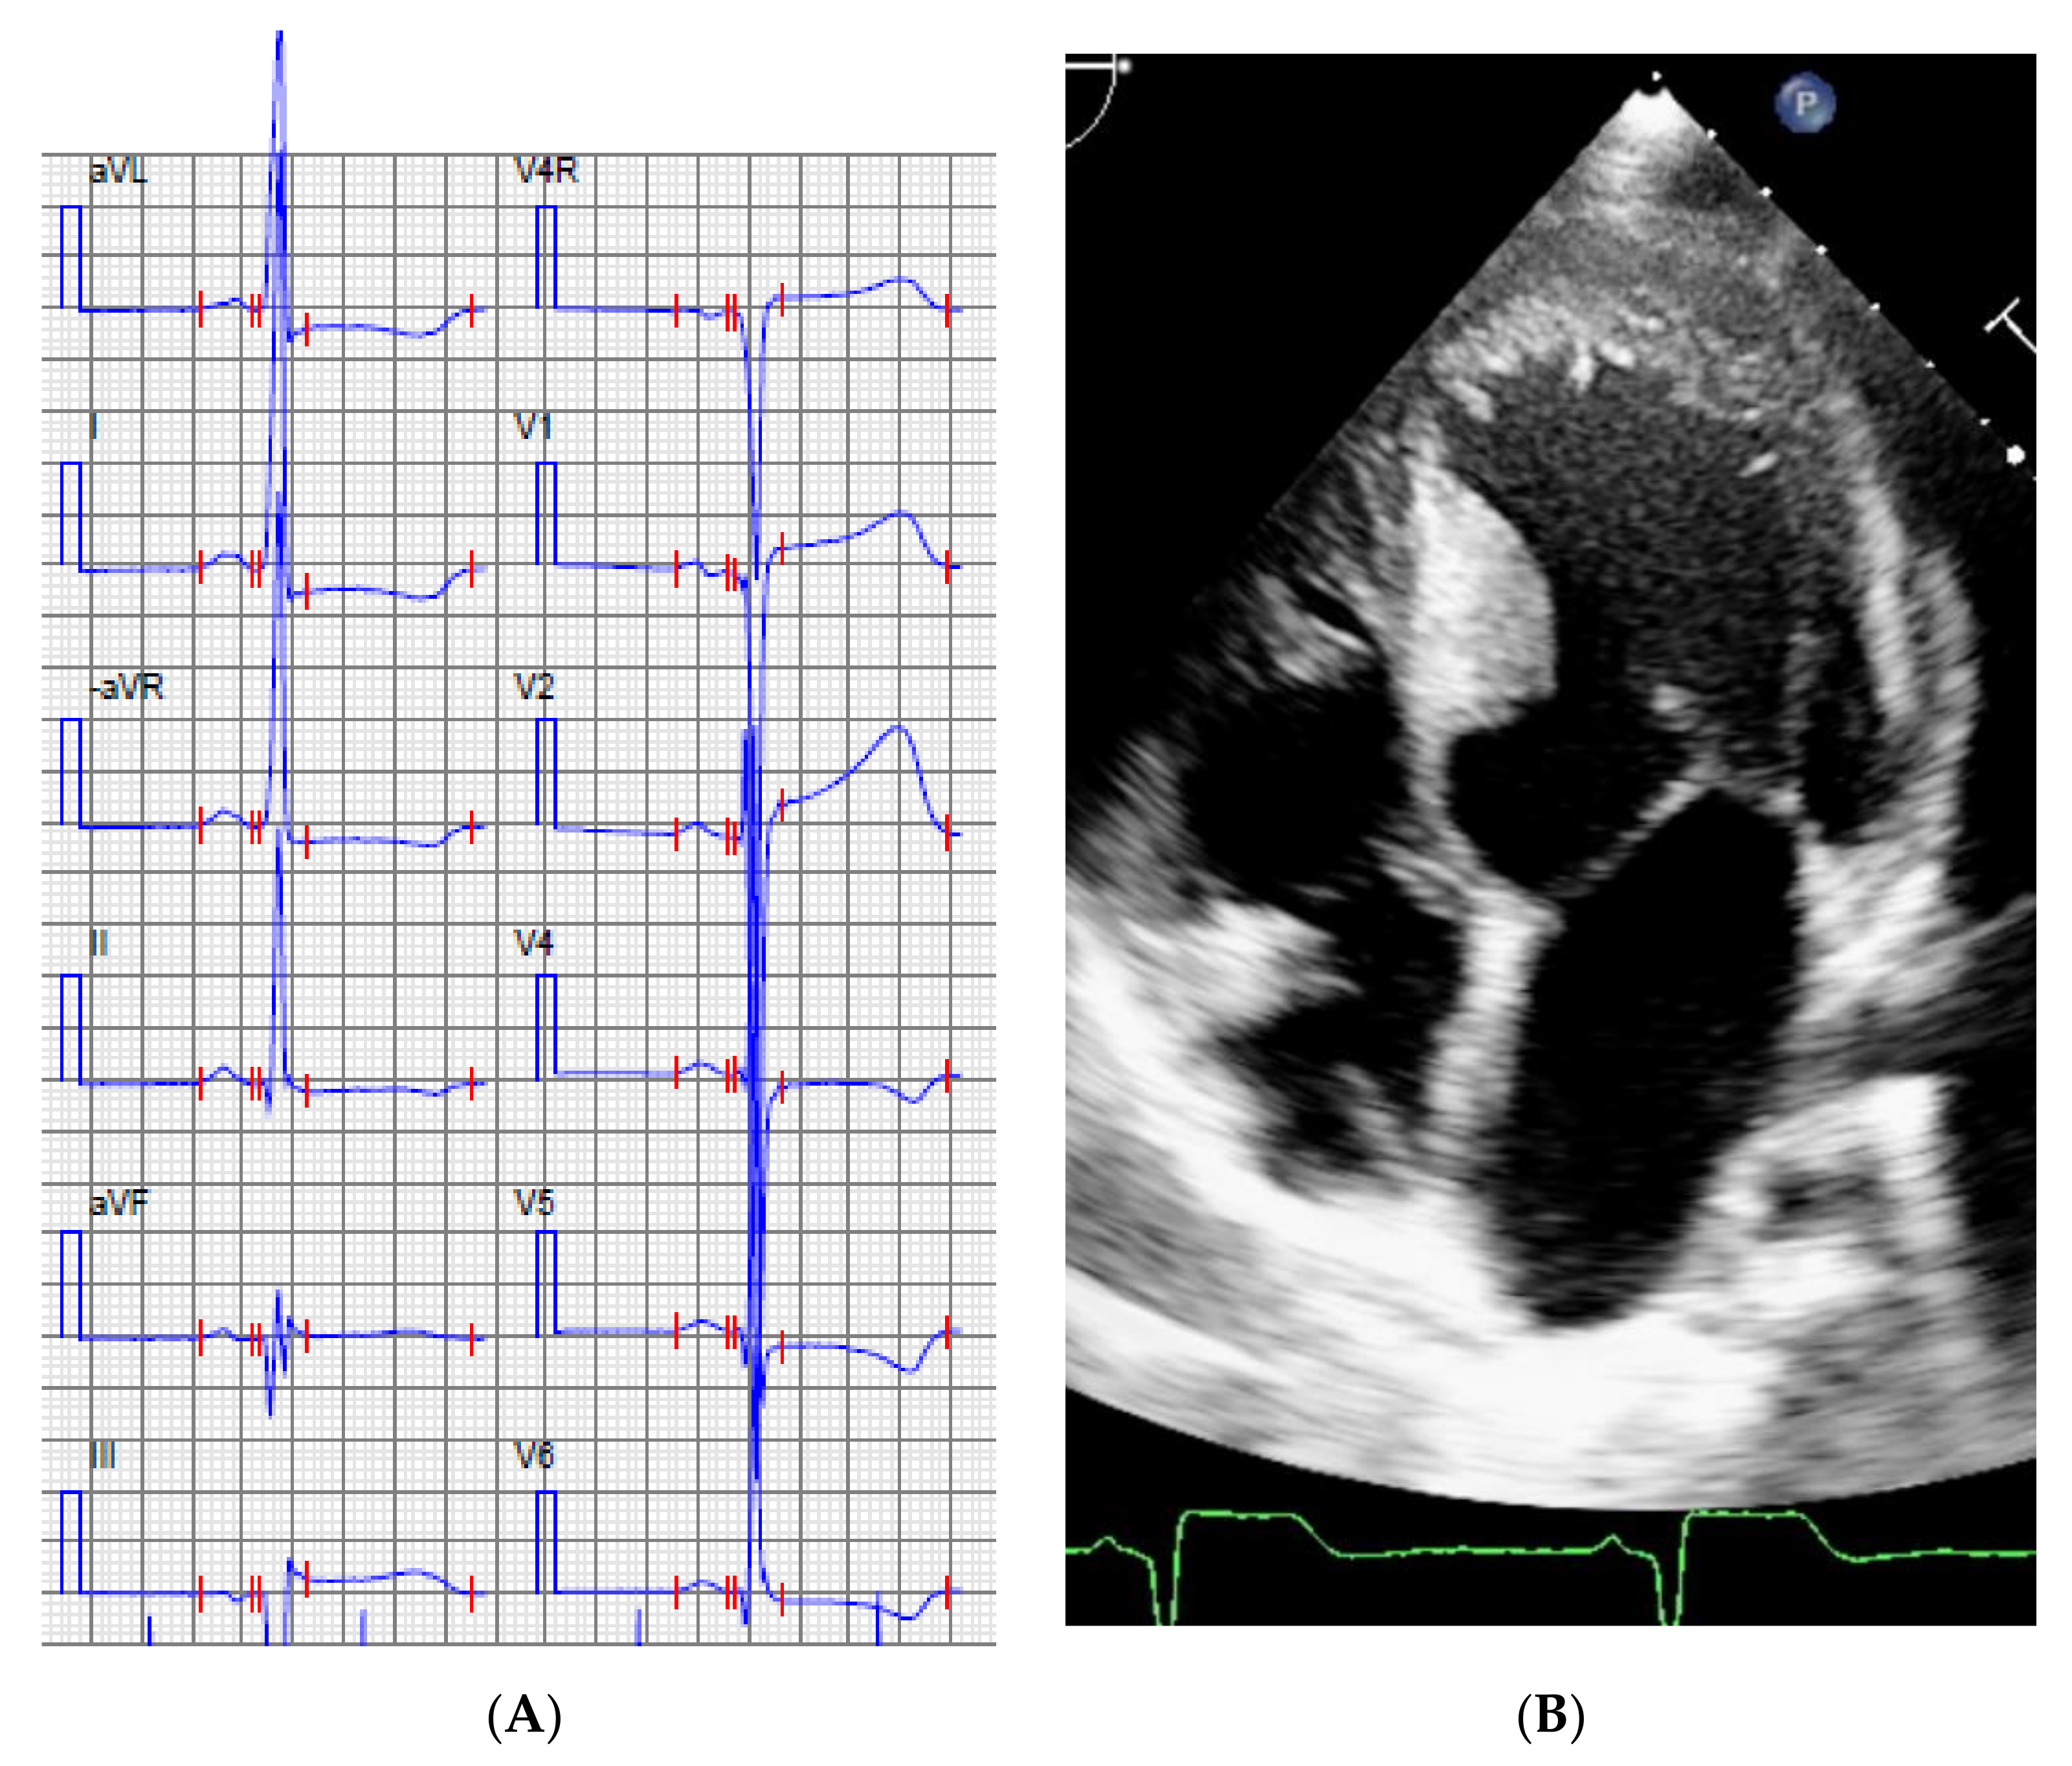

| 3. | II:1 | 14 | M | 0 | First symptom pro-longed QTc, rapid evolving to HCM ASH and LVNC. | 2 | 3 | Mother mVSD, LVNC | ABCC9 Chr12(GRCh37):g.21997457A>C, NM_005691.3:c.3275T>G p.I1092S | PP3 VUS/Yes |

| 6. | II:6 | 11 | F | 2 | HCM/RCM | 3 | 13 | Index patient and brother with SCD as first symptom | PGM1 Chr1(GRCh37):g.64100506G>A, NM_002633.2:c.689G>A, p.G230E | PM2 + PP3 + PS3 Pathogenic/Yes |